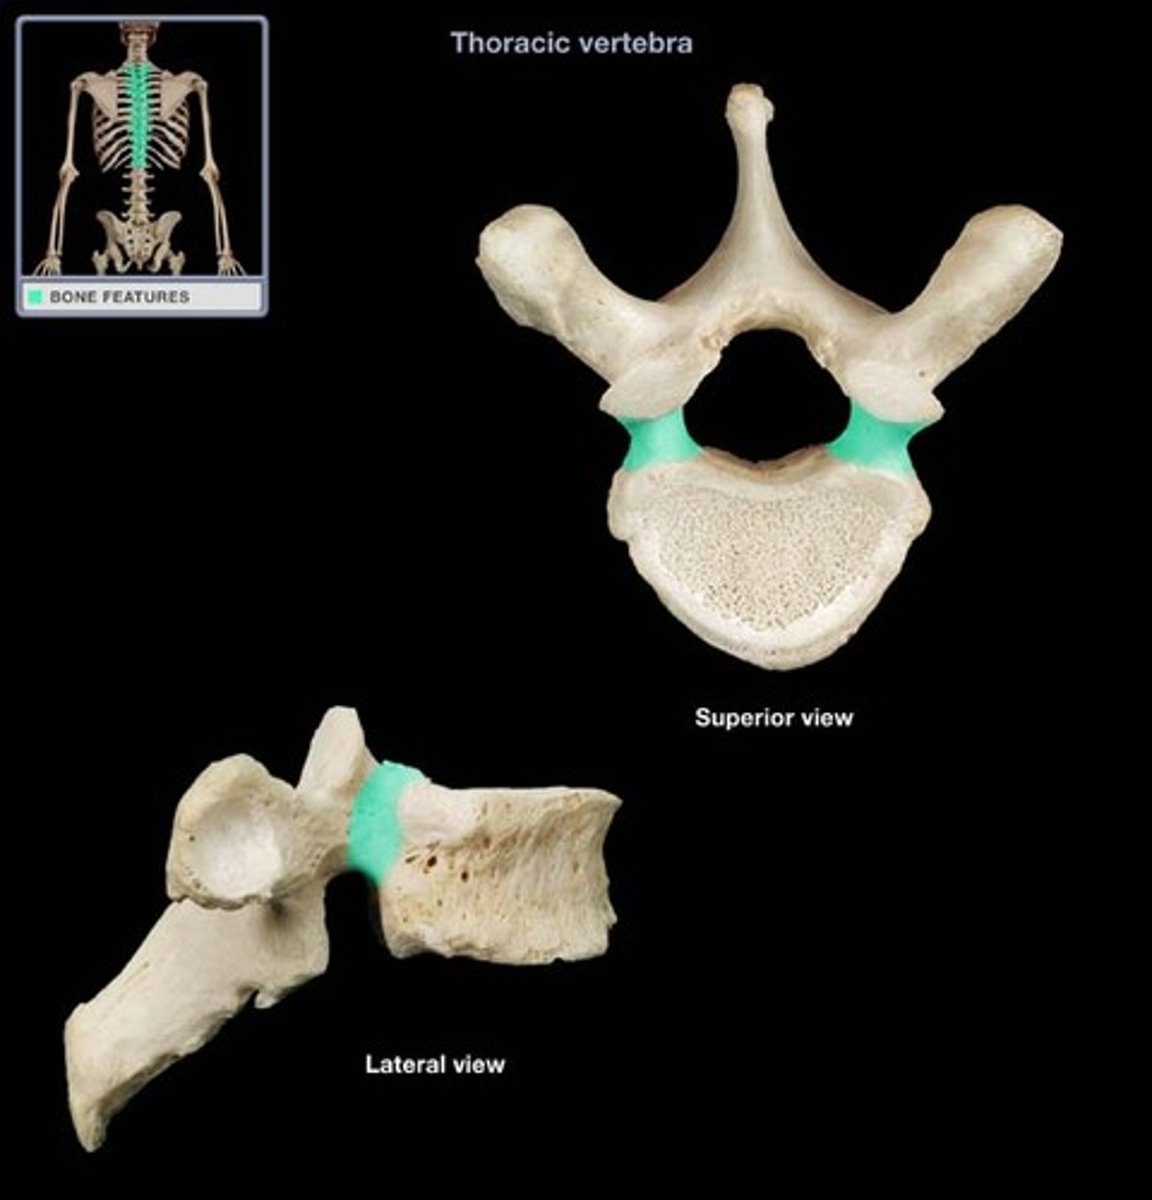

transverse costal facet

rib articulation (attachment) ONLY FOUND IN T1-T12

what is the purpose of the transverse costal facets

12 (T1-T12)

how many transverse costal facets for rib articulation (attachment) are there

transverse costal facets (articulations) where ribs attach to

what differenciates the T spine vertebra